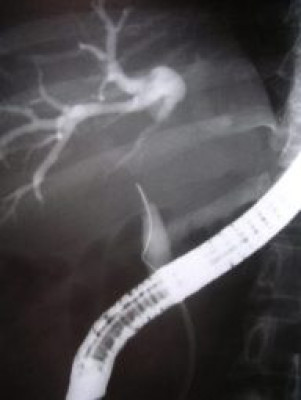

Colagiopancreatografía Retrógrada Endoscópica (ERCP)

Envíado por Gastroclínica